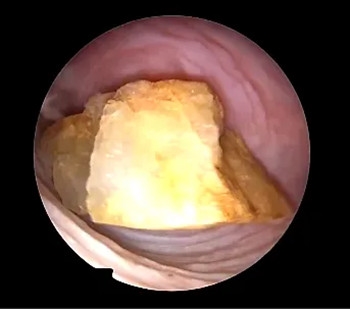

术后再次进镜后见阴道中段

前后壁及侧壁粘膜均见异物侵蚀后损伤

术后10天、15天检查

术后再次行宫腔镜下阴道内镜检查发现阴道中段封堵性粘连,镜下分离粘连后,阴道基本恢复正常,采取防止粘连措施,嘱咐小馨妈妈10天后再行复查。复查时宫腔镜下见小患者阴道形态恢复正常,各壁创面基本恢复正常。